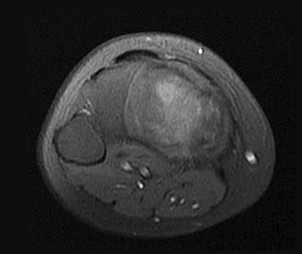

Figures 6a through 6d are the radiographs and T1-weighted sagittal and fat-saturated axial MR images of an otherwise healthy 56-year-old man who has anterior knee pain and intermittent swelling after sustaining a noncontact twisting injury. Low-power and high-power hematoxylin and eosin stained histologic specimens are shown in Figures 6e and 6f. Based on the history, radiographs, CT scan, MR imaging, and histologic findings, what is the most likely diagnosis?

The lesion in the posterior intercondylar knee notch is a benign synovial hemangioma. Intralesional calcifications, classically associated with hemangiomas, are frequently not identified on plain radiographs. The MR imaging reveals a hypervascular lesion with multiple filling defects, with hyperintensity on T2-weighted images and low-to-intermediate signal intensity on T1-weighted images. Histologically, vascular lakes within fine capillaries with a synovium on the surface of the lesion are characteristic of this condition. Many patients with synovial hemangioma have pain, swelling, stiffness, or mechanical symptoms. The correlation of symptoms with the hemangioma for this patient is unclear because there was recent trauma and a concurrent meniscus tear. Simultaneous treatment of both potential sources of pain is typically recommended. As with PVNS, the disease can be localized or diffuse. Surgical excision, either open or arthroscopic, is the recommended treatment. PVNS is the most common intra-articular tumor, but hypointensity in either the diffuse or localized type is characteristic in both T1- and T2-weighted images. Synovial sarcoma, although often found close to a joint, is not characteristically found within a joint.